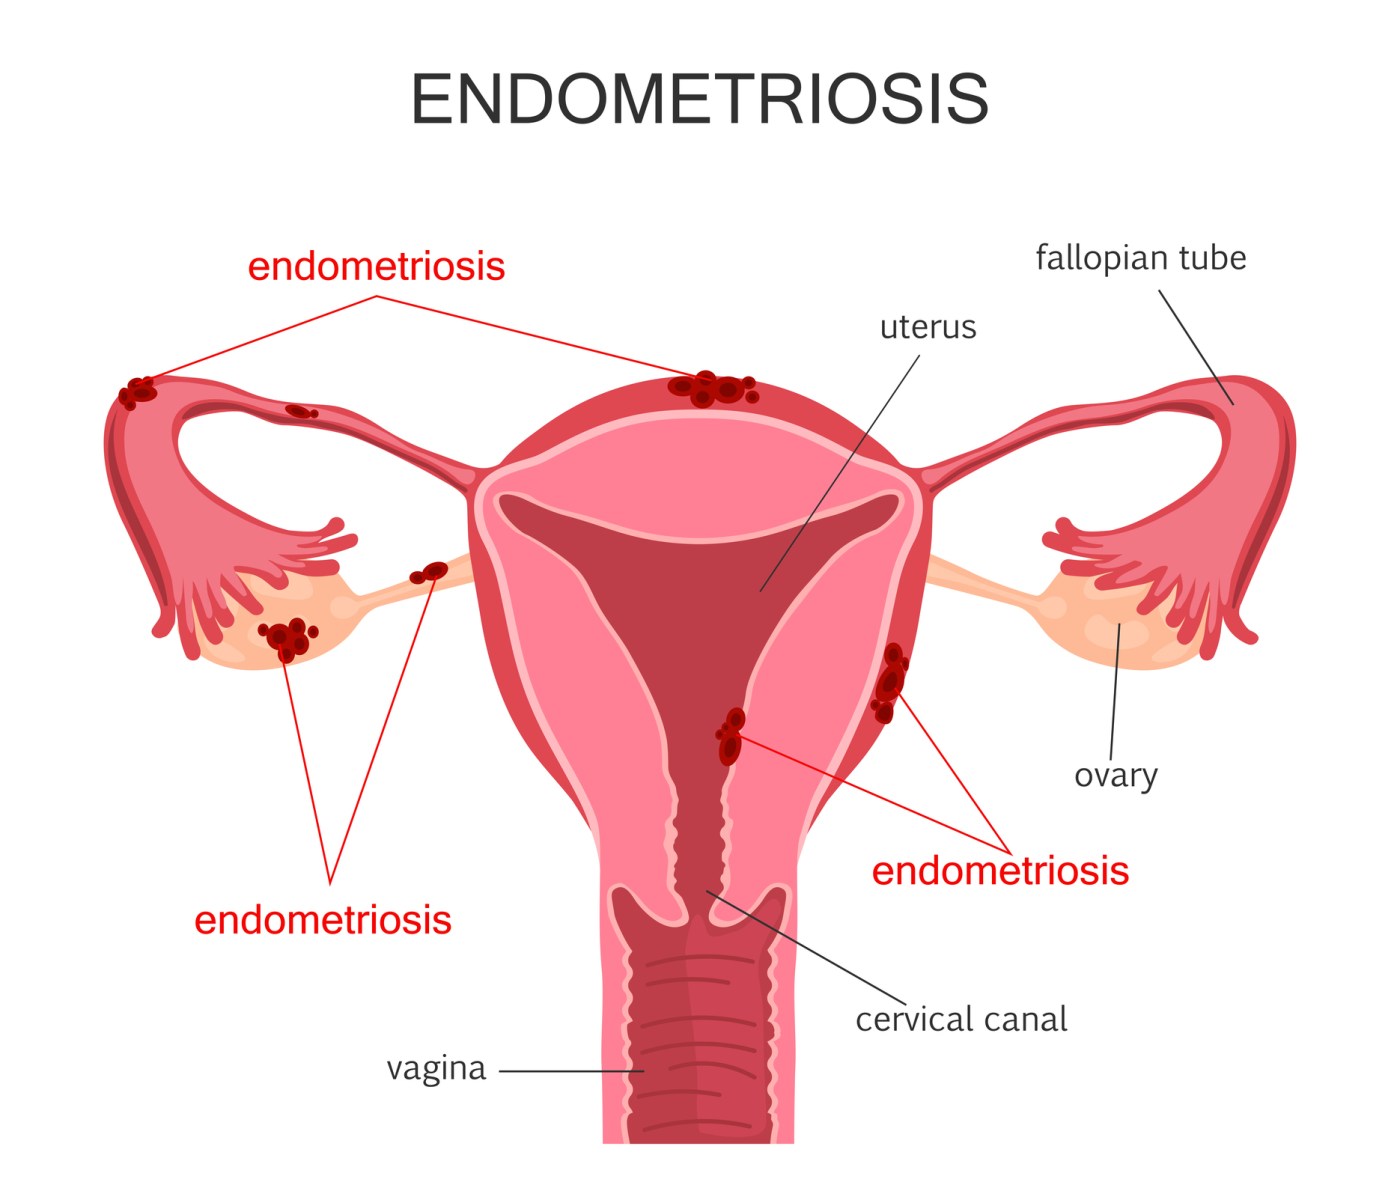

Continuar lendo “Introdução Alimentar Infantil”De acordo com dados do Ministério da Saúde, a endometriose afeta de 10% a 15% das mulheres em idade reprodutiva no Brasil. Isso significa que, aproximadamente, 7 milhões de mulheres brasileiras são diagnosticadas com a doença.

A endometriose é uma doença inflamatória crônica que ocorre quando o tecido endometrial, que normalmente reveste o útero, cresce fora do útero. O tecido endometrial pode se desenvolver nos ovários, trompas de falópio, intestino, bexiga, reto e outros órgãos.

Os sintomas da endometriose incluem dor pélvica, cólicas menstruais intensas, dor durante a relação sexual, infertilidade e dor ao evacuar ou urinar.